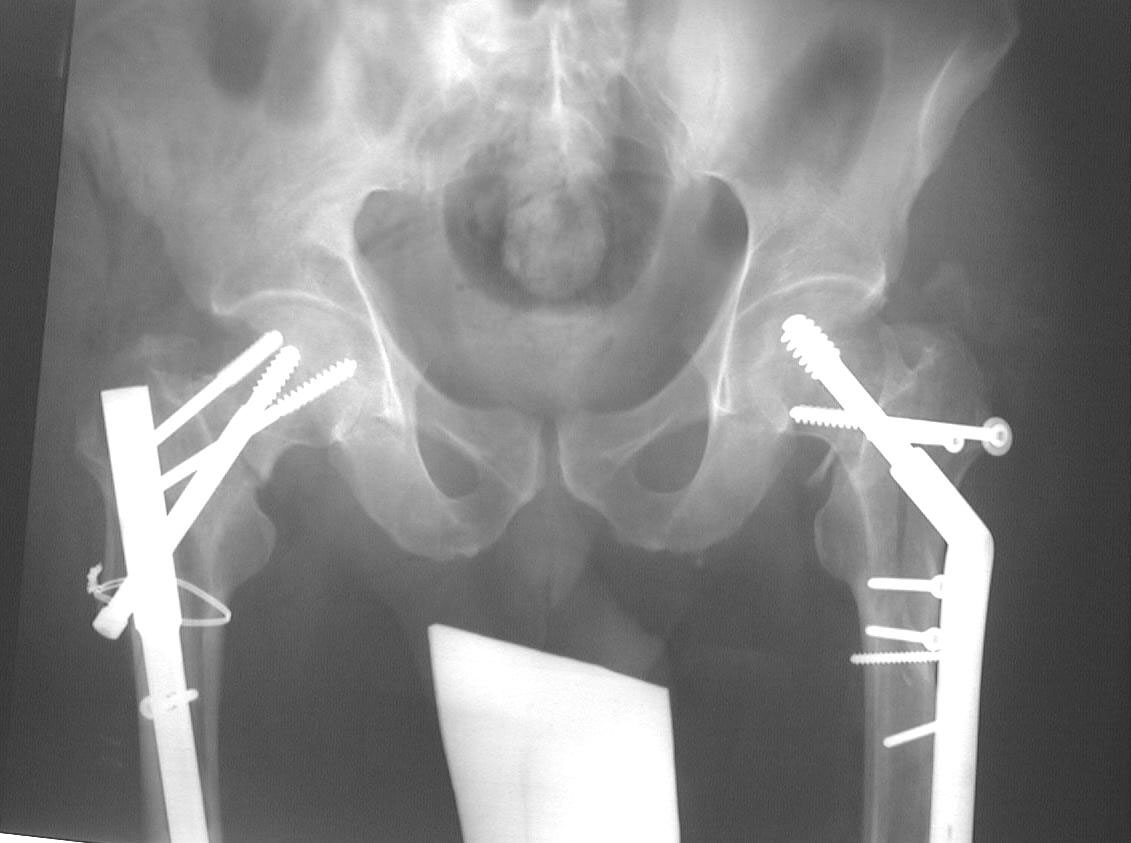

Attached here few x-rays of a multi-trauma patient. He is a 51years old man,sustain MVA at 08/15/99 and refer to our hospital few days ago, more than twoweeks after injury. He sustain Bilateral femoral fracture including femoralneck, A right humerus fracture, right distal radius fx, left open ulnar fx,right tibial plateau (type III) fx and Chopart fracture dislocation of the rightfoot. At the other hospital where he was admitted, He underwent laparotomy andfixation of both femur by reconstruction IMN, application of Ex Fix to thehumerus, and reduction and K.W. fixation of the Rt foot. He is currently stable and conscious. He is scheduled next week for replacing of the Rt IMN to aretrograde nail and pinning (6.5 mm screws) of the neck fracture, fixation ofthe ulna, distal radius and tibial plateau.

AP Pelvis

We fluoroscoped every thing in the OR under anesthesia. It was clear that the Ltproximal side is unstable, in mal-position and the nail is probably outproximally.

On the Rt side, the proximal construct was stable but the distal (the shaft fx)was not.

We decided to fix the Lt femur with a few lag screws on the proximal part andstabilize the femur with long Richard plate that was inserted in a sub-muscularfashion, in order to avoid opening the main shaft fx (the so-called biologicfixation - see Lt leg incisions.).

On the Rt side I replaced the recon nail with a longer one (accepting its toolateral and anterior entering point), I added a proximal locking screw (anterior toposterior) in the subtrochanteric region through a self-made extra hole, and two 6.5cancellous hip screws posterior to the nail.